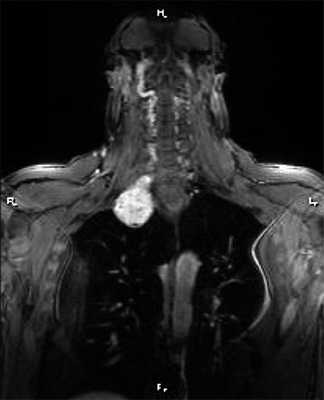

При опухолях верхней апертуры (цервико-медиастинальные опухоли), исходящих из ветвей плечевого сплетения и с локализацией >50% ее объема на шее (рис. 3), операцию начинали с надключичного доступа.

Рис. 3. Магнитно-резонансная томограмма пациента с цервико-медиастинальной нейрогенной опухолью, проникающей в средостение через верхнюю апертуру, фронтальный срез.

Надключичный доступ начинали от яремной вырезки и продолжали до трапециевидной мышцы под углом 45° по отношению к ключице (рис. 4). Этот доступ малотравматичен, обеспечивает прекрасный контроль магистральных сосудов и плечевого нервного сплетения, и в случае необходимости (при крупных опухолях, угрозе кровотечения) разрез продляли на грудину с последующей частичной стернотомией (стерноторакотомией) или дополняли ВАТС в случаях трудности мобилизации внутригрудного компонента.